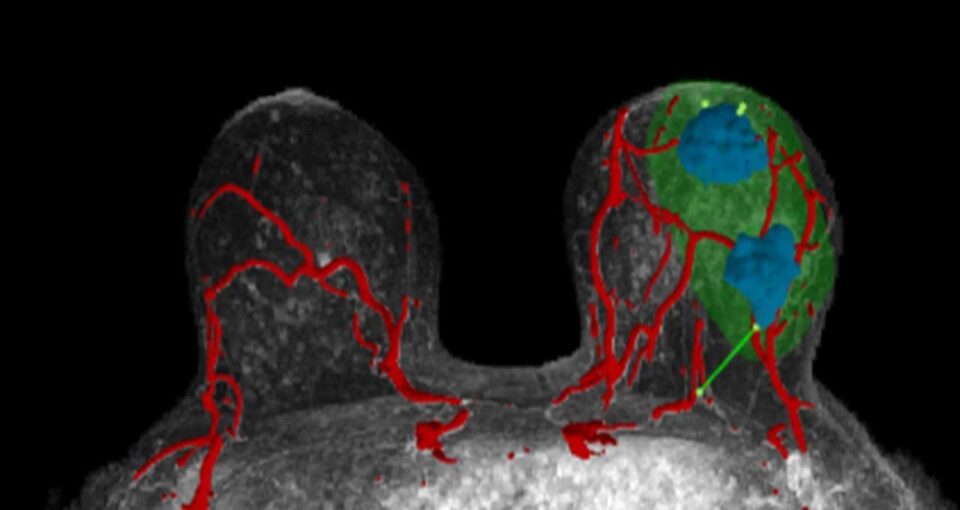

Supporting Surgeons

Illinois-based startup SimBioSys has created TumorSight Viz, a technology that converts MRI images into 3D models of breast tissue. This helps surgeons better treat breast cancers by providing detailed visualizations of tumors and surrounding tissue.